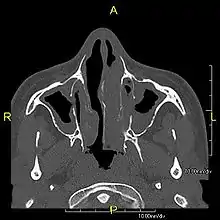

عندما يكون خلل الحركة الهدبي الأولي ترافقه أعراض التهاب الجيوب المزمن وأحشاء مقلوبة الموضع وتوسع القصبات فإنه يدعى بمتلازمة كارتاجنر.